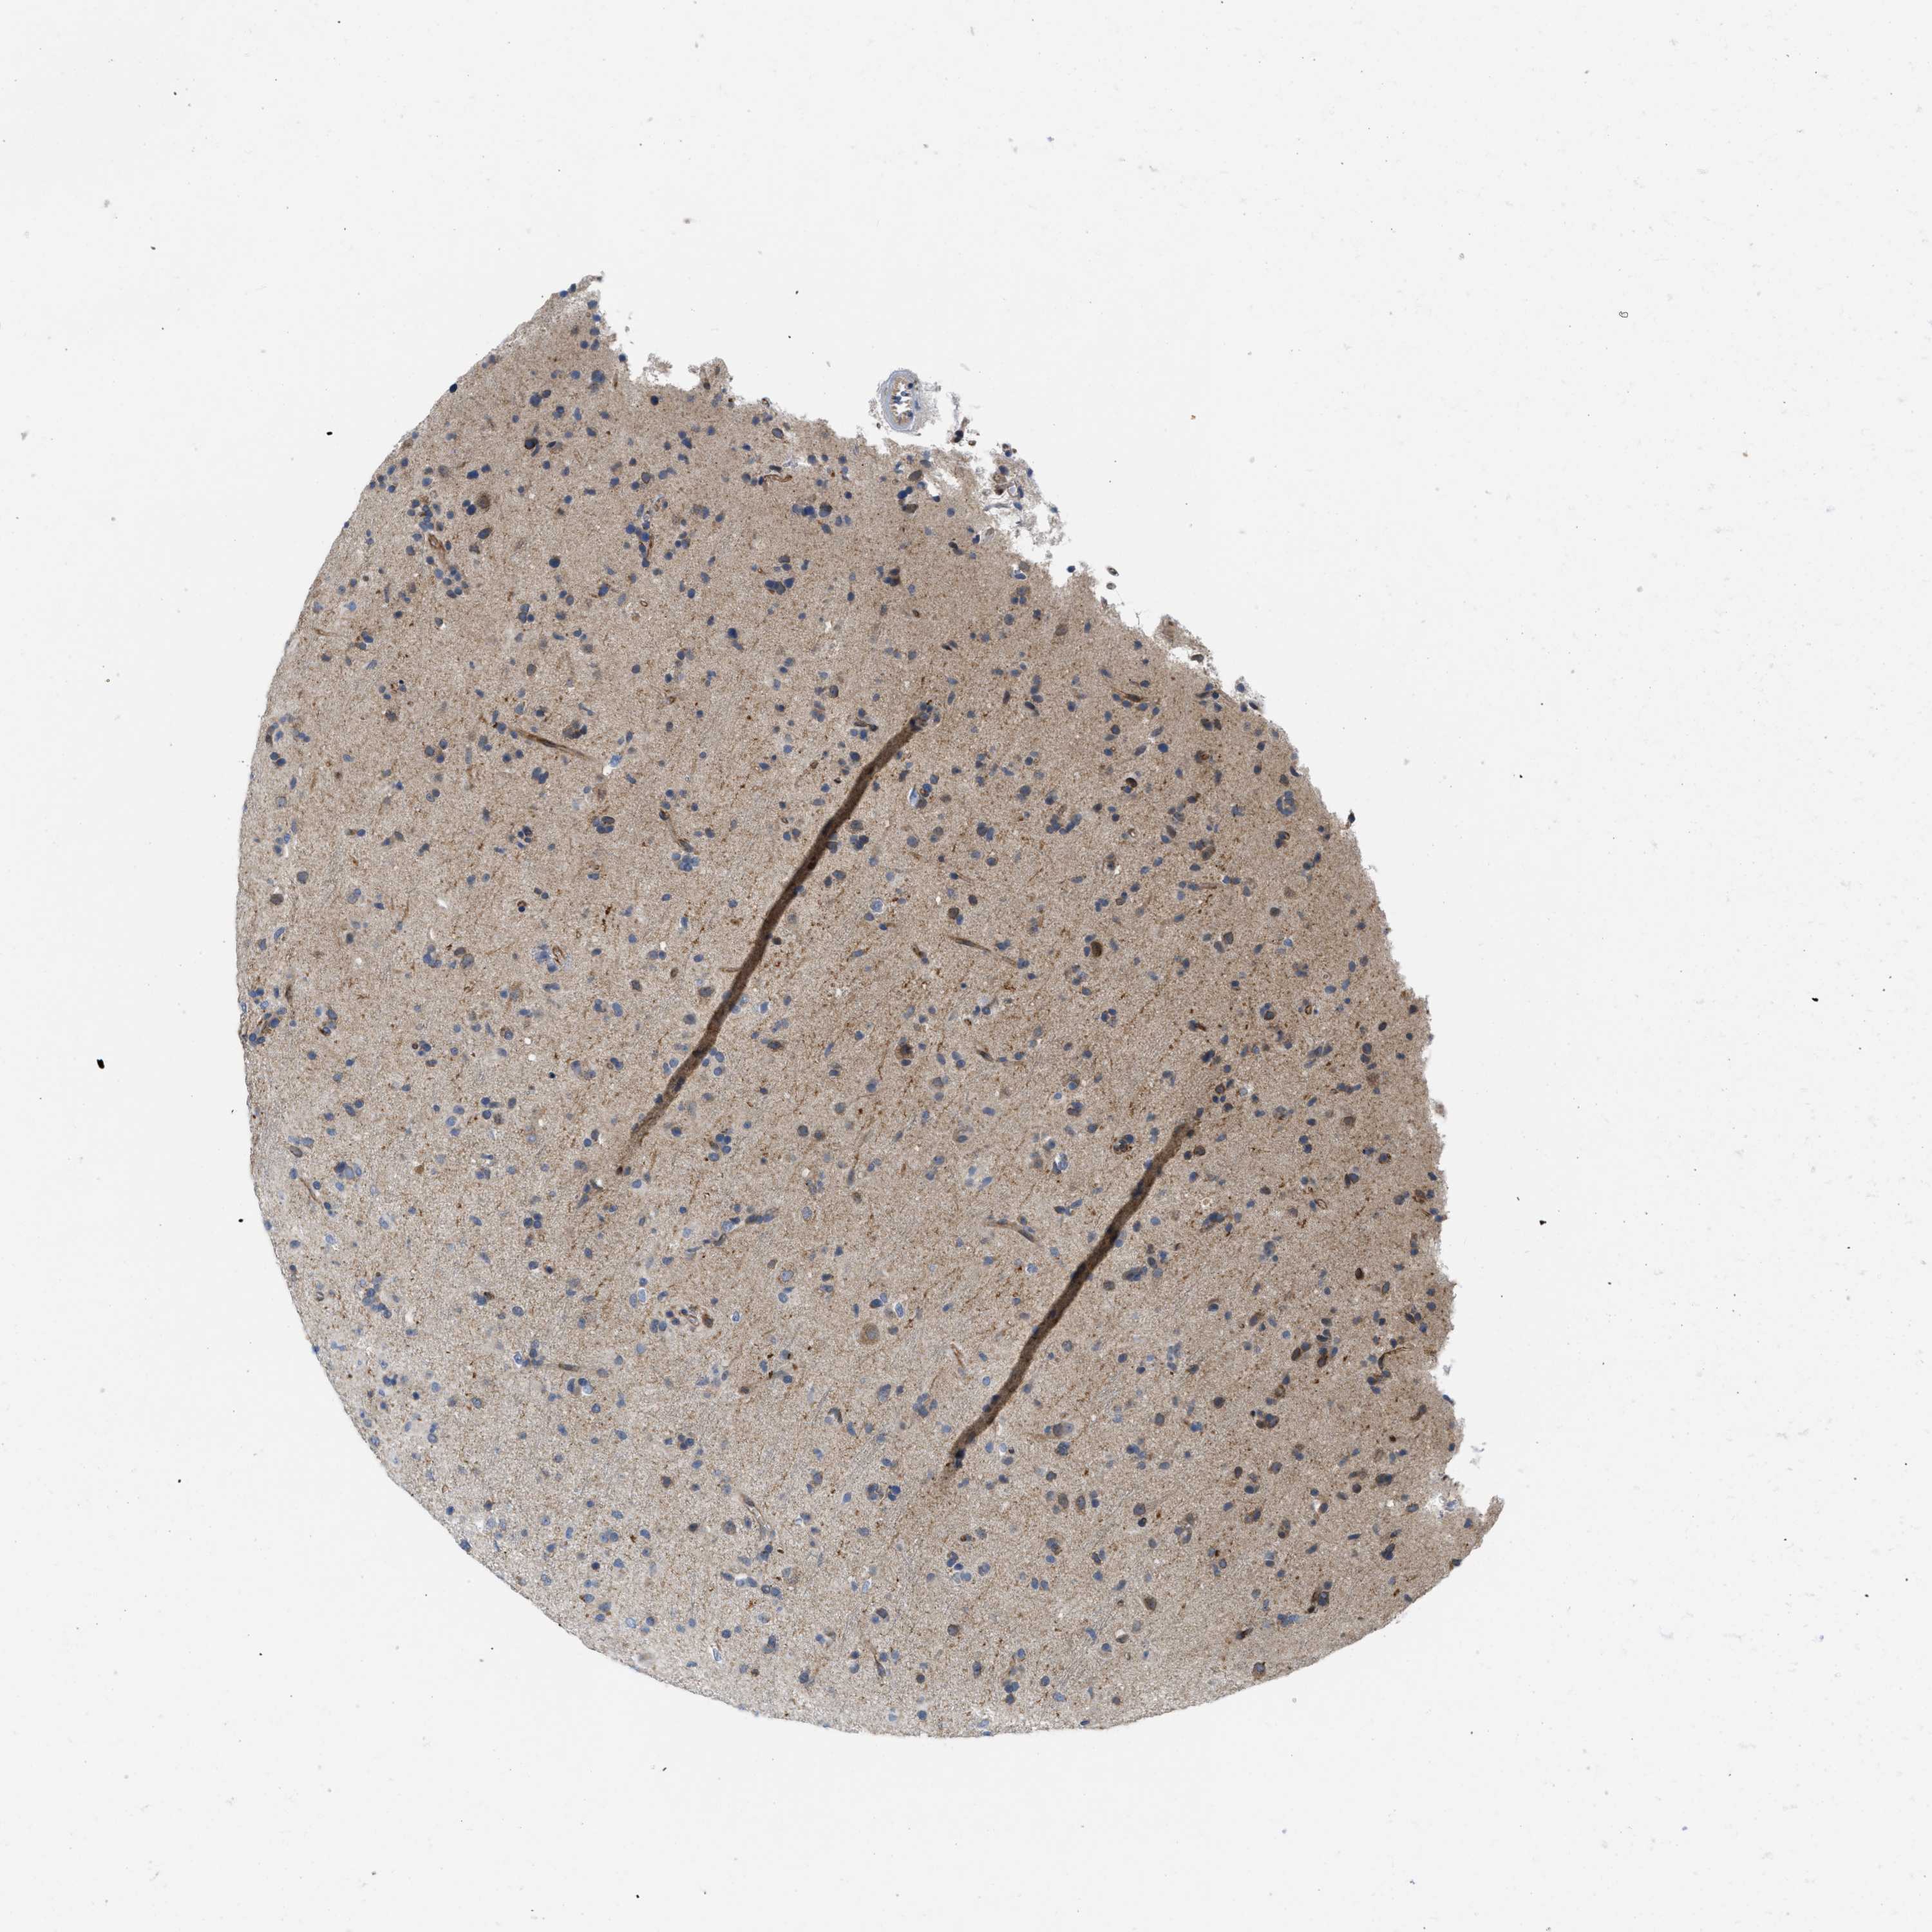

GLIOMA - Protein expressioni

A mouse-over function shows sample information and annotation data. Click on an image to view it in a full screen mode. Samples can be filtered based on level of antibody staining by selecting one or several of the following categories: high, medium, low and not detected. The assay and annotation is described here.

Note that samples used for immunohistochemistry by the Human Protein Atlas do not correspond to samples in the TCGA dataset.

Antibody stainingi

Antibody staining in the annotated cell types in the current human tissue is reported as not detected, low, medium, or high, based on conventional immunohistochemistry profiling in selected tissues. This score is based on the combination of the staining intensity and fraction of stained cells.

Each image is clickable and will lead to virtual microscopy that enables deeper exploration of all samples and also displays staining intensity scores, fraction scores and subcellular localization as well as patient and tissue information for each sample.

Antibody HPA019460

Staining

High

Medium

Low

Not detected

Intensity

Strong

Moderate

Weak

Negative

Quantity

>75%

75%-25%

<25%

None

Location

Nuclear

Cytoplasmic/membranous

Cytoplasmic/membranous,nuclear

Glioma, malignant, High grade

Glioma, malignant, Low grade